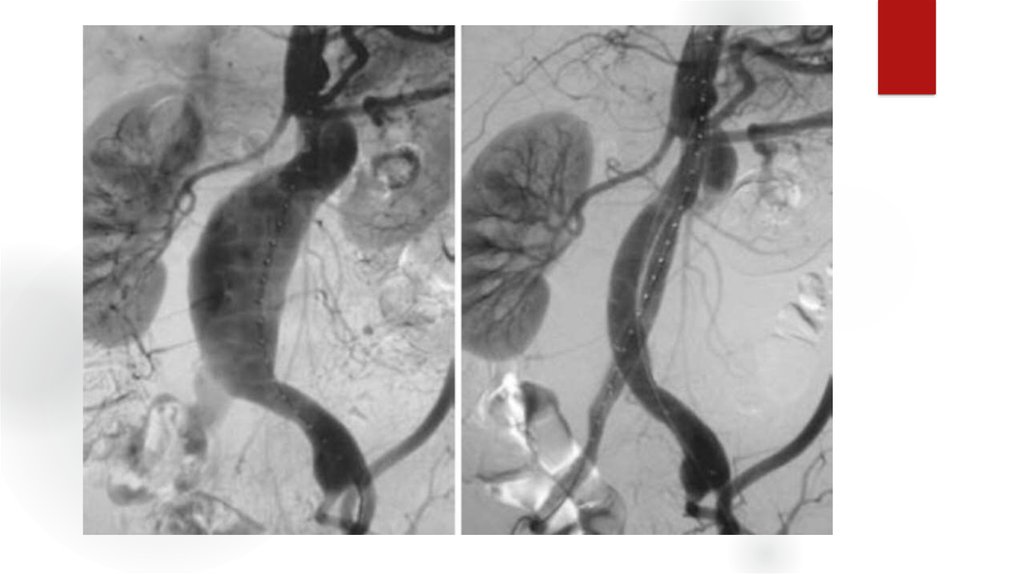

24. Оценка ангиограмм

Критерии:

- Окклюзии, их локализация

- Сегментарный уровень

- Степень

- Длинна пораженного участка

- Конфигурация и анатомия

- Количество пораженных артерий

- Морф.тип стеноза

- коллатеральное кровообращение